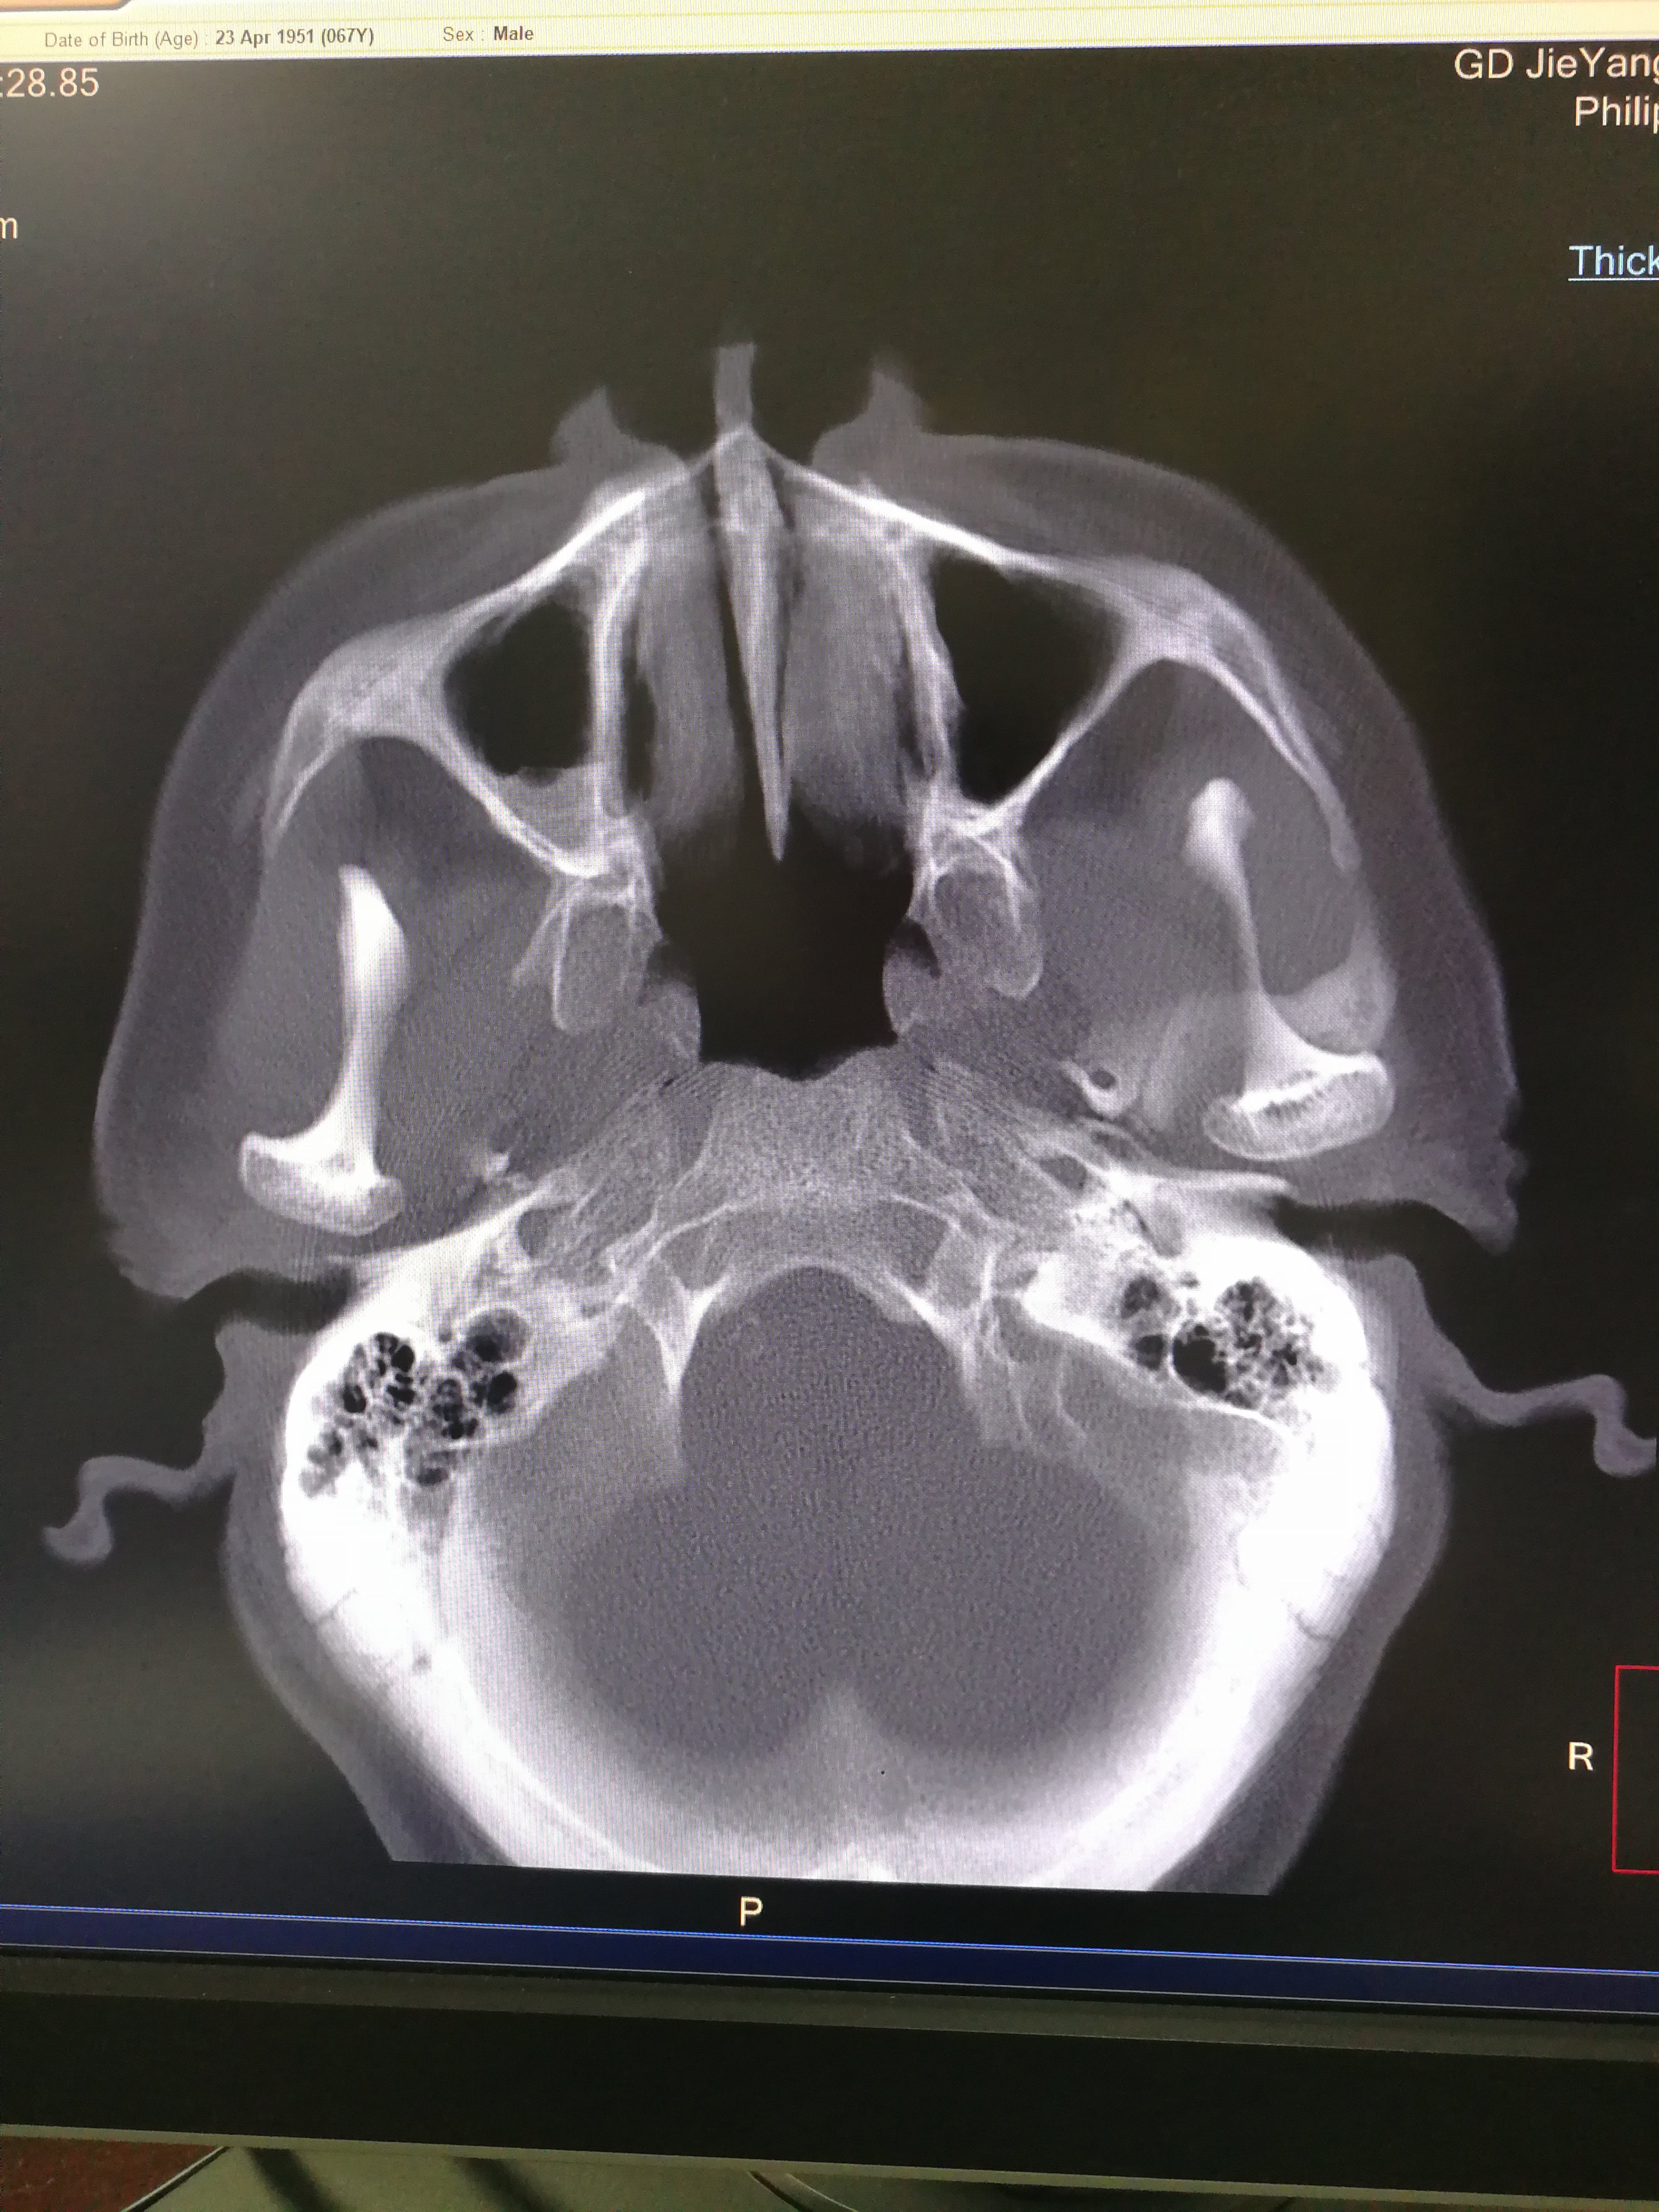

【求助】颞骨ct平扫

图片尺寸639x428

颞骨ct 水平位

图片尺寸2667x2000